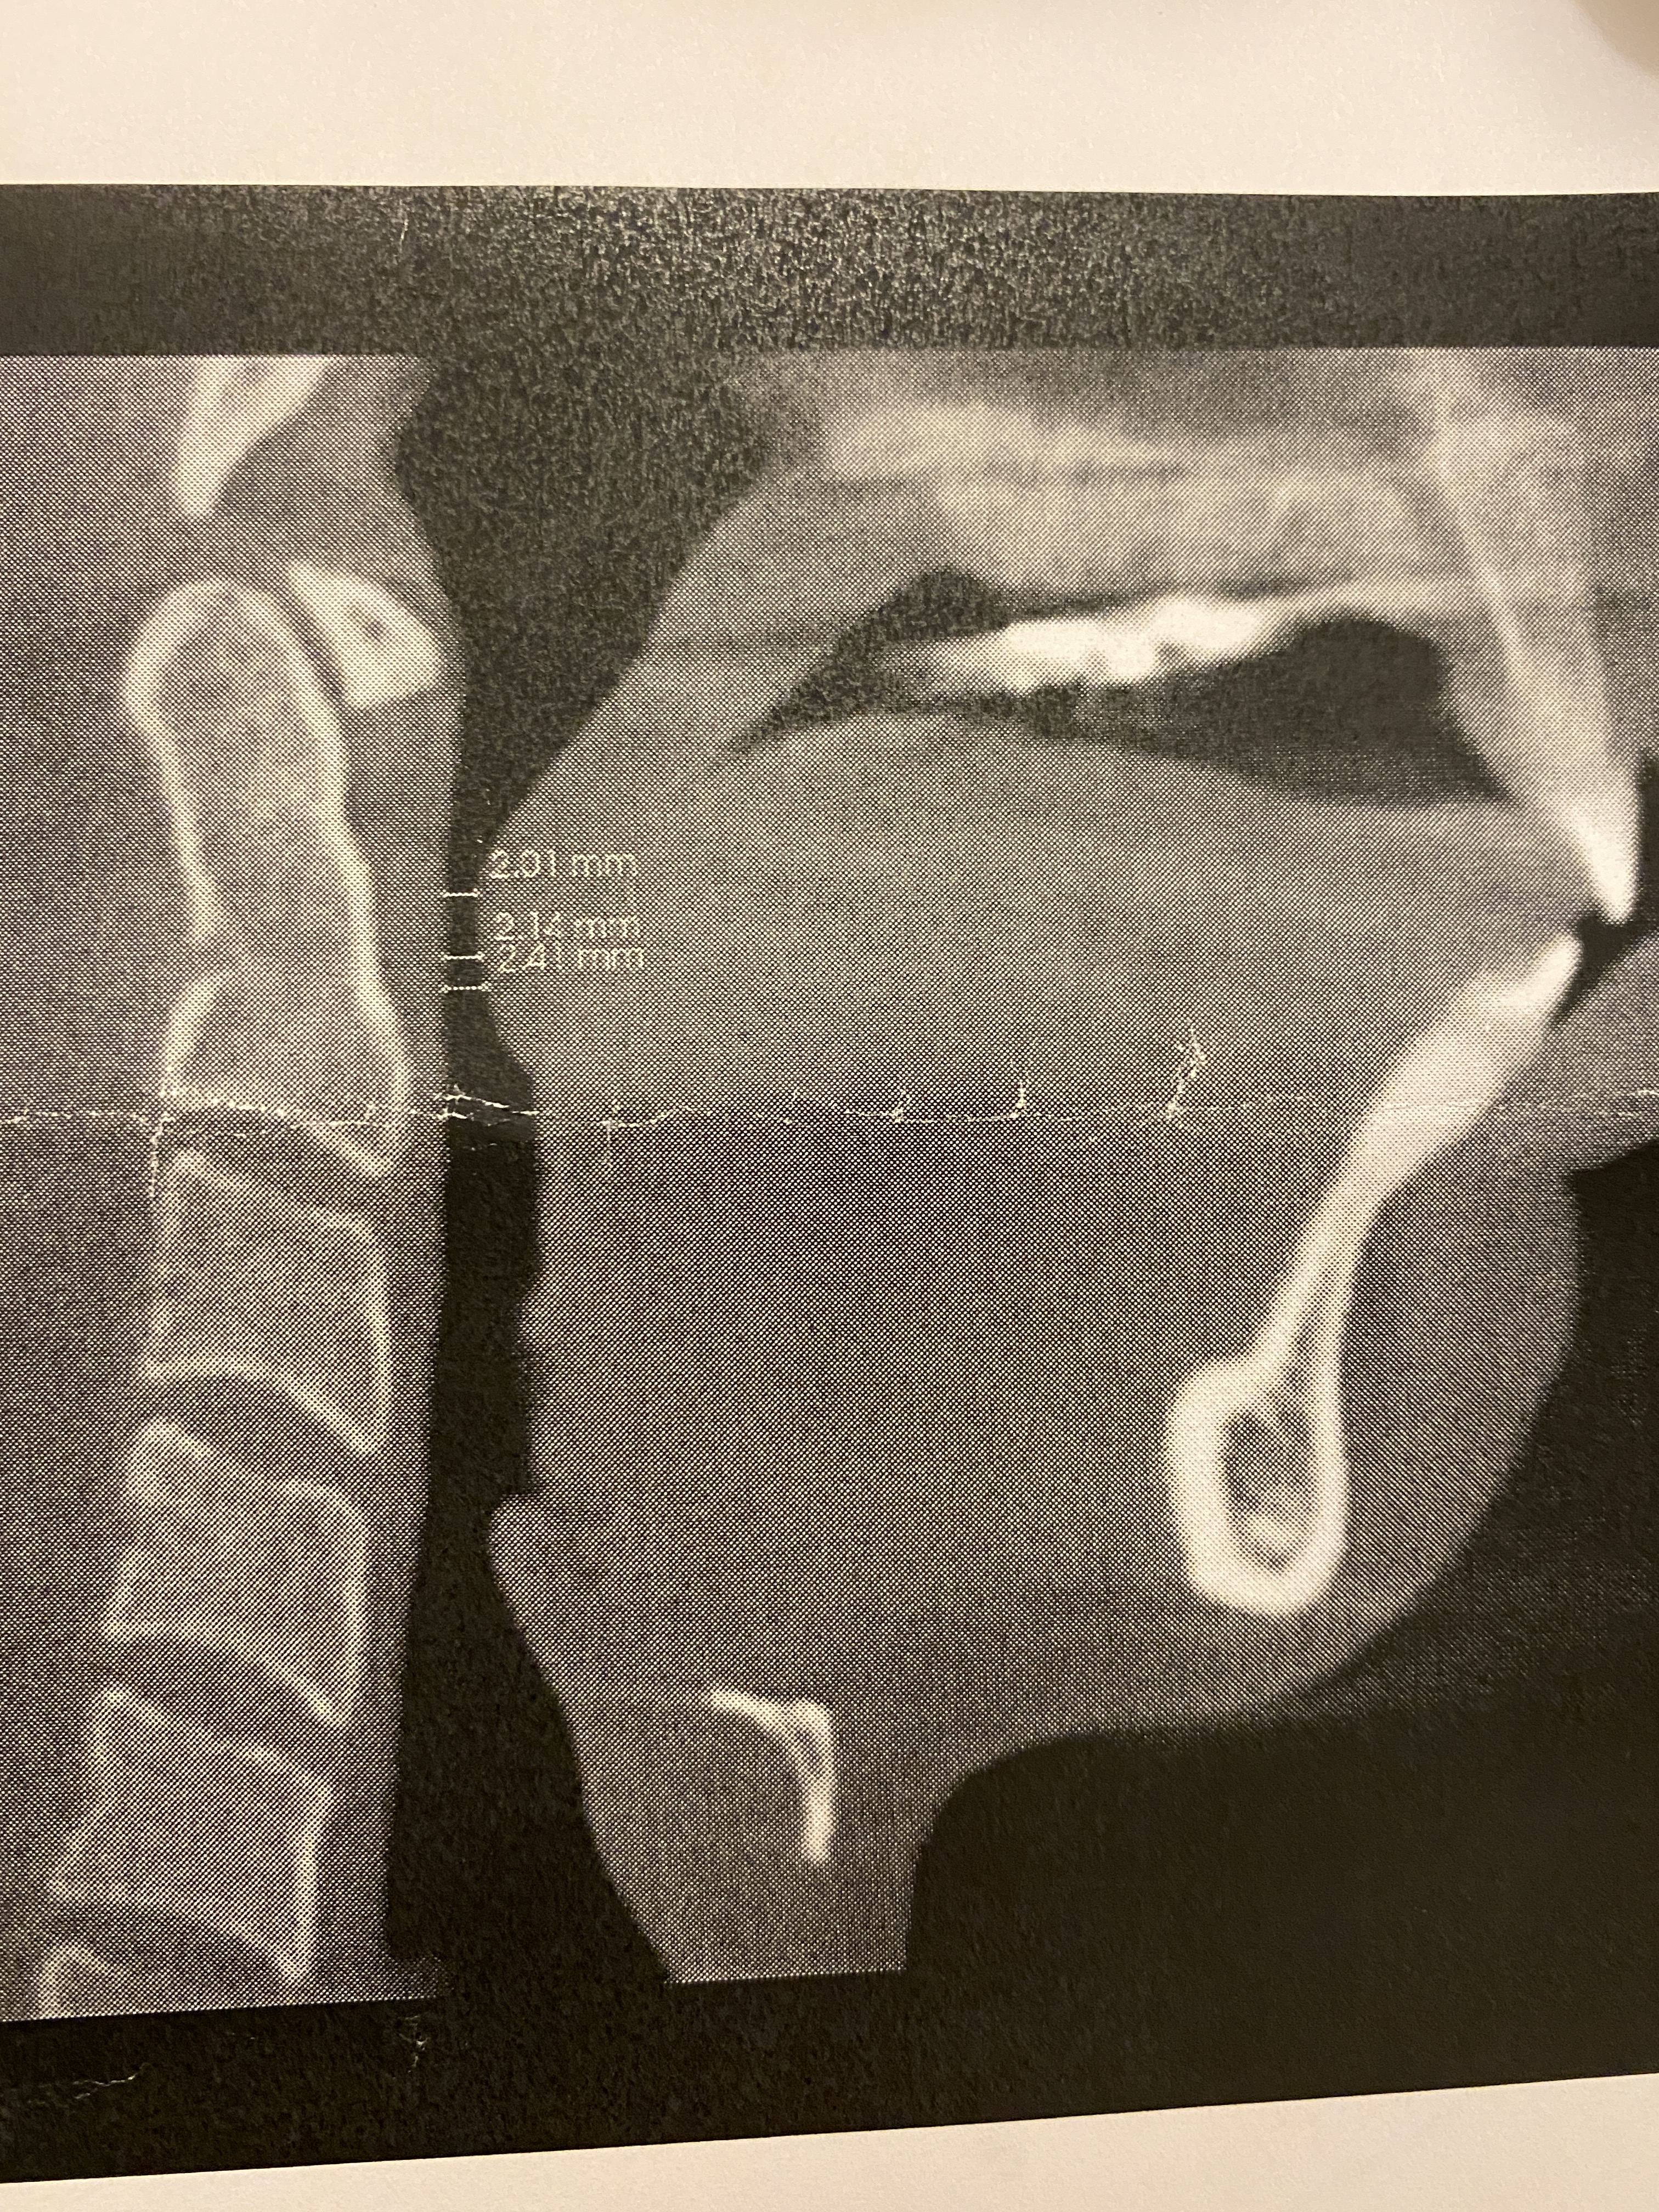

- Airway: Before I had TJR, my airway was 2mm at the narrowest point as

measured by my sleep doctor, which made sense why,

measured by my sleep doctor, which made sense why,- I struggled to swallow pills

- My oxygen levels would drop at night and I was diagnosed with UARS (Upper Airway Resistance Syndrome)

- Received 50% less REM sleep compared to other healthy adults in my sleep test

- 1-3 times a month would wake up choking/gasping (that I could remember), and snored a little. I always slept on my side and never on my back to make breathing easier. I was a stomach sleeper on and off age 12-16, I at one point thought that had caused my TMJ issues 🤷♀️ (could have…). Usually ICR is the perfect storm of many things and not one singular thing.

- I would hyperventilate with extreme cardio exercise ( I thought I was dying one time, literally was on the gym floor sobbing and gasping). I once had a jaw surgeon tell me that “dentists were real ‘hot’ on this airway stuff” but he didn’t seem to think it accounted for much. He also accepted that he just had not studied it enough yet. I think it is all it is made out to be, but time will tell as this year progresses and I can see if any of my fatigue, mental fog and anxiety levels go down with better quality sleep.

- Forward Head Posture/ cervical spine: As the mandible dips back from ICR, it presses on the airway causing the head to tilt forward and the neck to crane in order to open up the soft tissue of the airway enough to receive adequate oxygen. I’m so thankful the body adapts, but these adaptations are not without consequences and many of the consequences we still don’t medically have a good grasp on to know just how far reaching they are to other systems in the body.

- My post op x-ray shows a straighter head posture! I have been seeing a chiropractor the past few years to help manage some of my chronic pain, so I imagine he will be very happy to see this!

- Lips are closed: It is HEALTHY to breathe through the nose and to have your lips closed. Those with ICR are unable to do this without muscle strain, which encourages mouth breathing. Mouth breathing causes all. kinds. of. problems. You can read more about them here if you are interested: https://www.endur.com/blogs/blog/8-scary-consequences-of-mouth-breathing